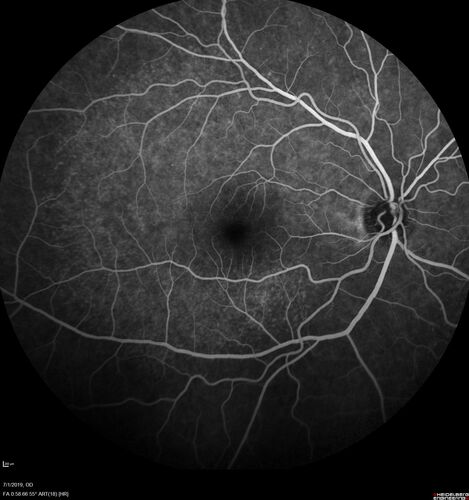

Ocular Lymphoma - Initially presented like auto-immune retinopathy

43 year old man: initial presentation - The vision in the left eye is blurry and opaque for about 2 weeks.  In the central of the vision, when he covers the right eye, in the center of the left eye there is a film with a light in the middle.  This has never happened before.  He has not been sick for the last few months.  A few weeks ago he saw waves on the floor when looking down but that has gone away.  Since the vision loss started the vision has not changed much.  The central vision is not getting better.

Labs normal.  One positive antiretinal antibody - Arrestin

VA improved over 2 months to normal.  Then the patient had 2 more episodes of self-limited vision loss (no treatment).  Then 2 years later he presented with a diagnosis of CNS lymphoma and later developed subretinal deposits (last images)